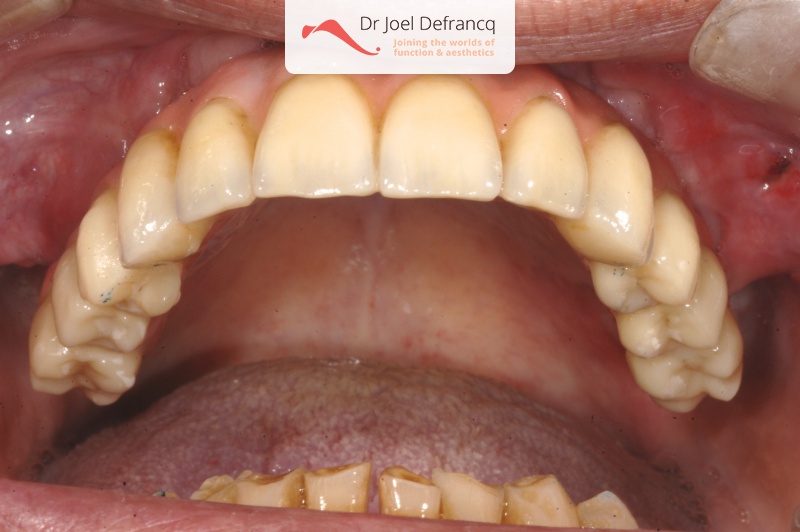

Dalon: fixed teeth in a week - implants

Behandeling tandheelkundige implantaten

- Vaste tanden op implantaten (bovenkaak)